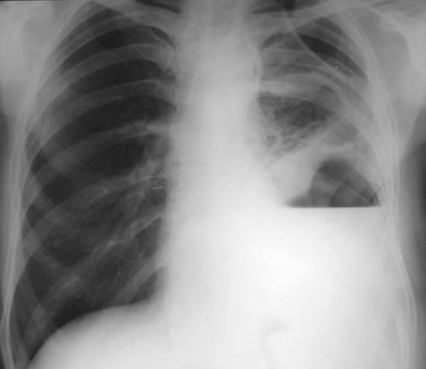

Rx toracică, incidență P-A

DESCRIERE:

la niv. întregului hemitorace stg → opacitate extinsă, nesistematizată, de intensitate mare, omogenă

caracter retractil → tracționează traheea și mediastinul de partea afectată

fără bronhogramă aerică

duce la micșorarea spațiilor intercostale

la niv. hemitoracelui controlateral → hipertransparență compensatorie

DX: atelectazie prin NBP central endobronșic (pe bronhia principală stg)

DD: pleurezie masivă → caracter expansiv